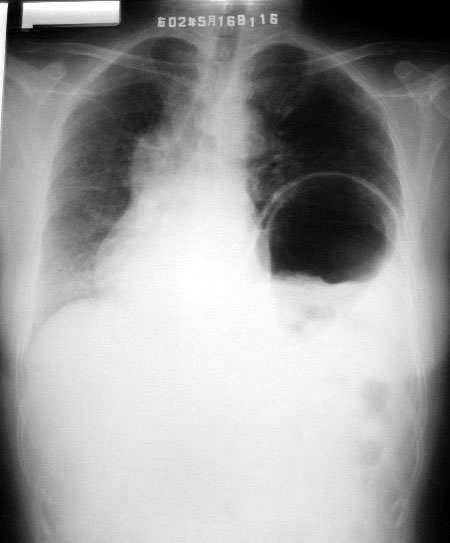

第一张02年

考虑隔疝

按楼主给出的片子时间,顺序说明病变有可恢复性及复发性,也只有左膈疝了,并且是可复性疝。

左侧隔疝.

典型左侧可复性隔疝

本例的诊断各位已经很肯定了---左侧膈疝。

膈肌有七个薄弱点:主动脉裂孔、下腔静脉裂孔、食道裂孔,及双侧对称的腰肋三角、胸肋三角。

膈疝常见于食道裂孔、胸肋三角、腰肋三角。

如果膈肌发育异常或后天外伤后破裂,可直接形成膈疝。

本例疝出的胃结构较大、较多,考虑为膈肌发育异常可能性大。经生理裂孔可能性小。

食道吞钡做得不完善,应该使胃部显影并加照卧位,找出疝环。

有没有可复性很难说,以前可复并不等于现在也可复,所以还是不要轻易下可复性疝。